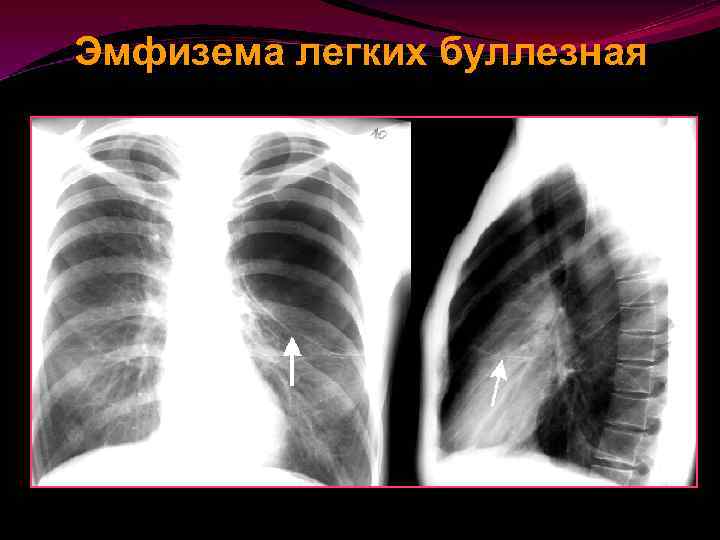

ЭМФИЗЕМА ЛЕГКИХ Буллезная 55 эмфизема легких характеризуется образованием воздушных пузырьков различных размеров (булл), которые локализуются, как правило, в краевых отделах легких. Эти пузырьки могут быть и единичными, и множественными, и распространенными, и локальными. Их размеры колеблются от 1 до 10 сантиметров.

Эмфизема легких буллезная Часто это проявление т. н. «Исчезающего легкого» легочной дистрофии

Эмфизема легких буллезная